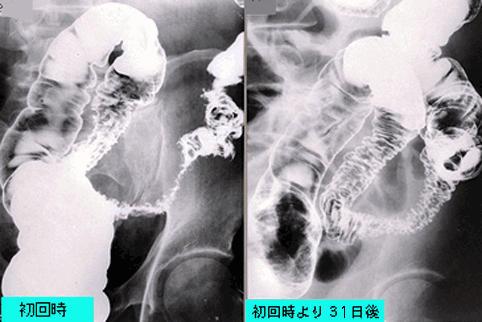

症例提示(所在地,施設名等): 東京都・ 国立がんセンター中央病院と九州がんセンターの共同作成

疾患(病理主体)の分類炎症性・潰瘍性疾患/その他

部位(臓器別)大腸/S状

検査方法X-P

病変の最大径(ミリ)40以上